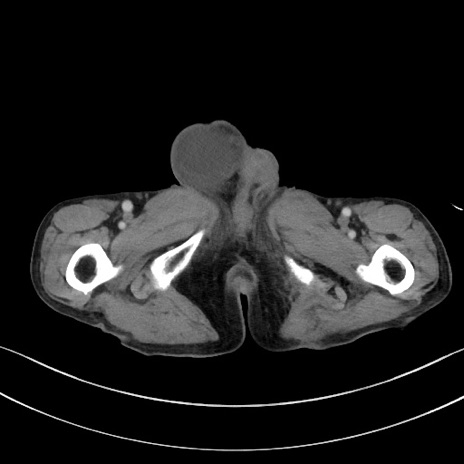

症例3(横断像)

【症例】 70歳代男性

【主訴】右鼠径部腫瘤、疼痛

【現病歴】本日朝より上記主訴あり、受診。

【既往歴】膀胱癌にて膀胱全摘、両側尿管皮膚瘻

【データ】WBC 5600、CRP 0.56